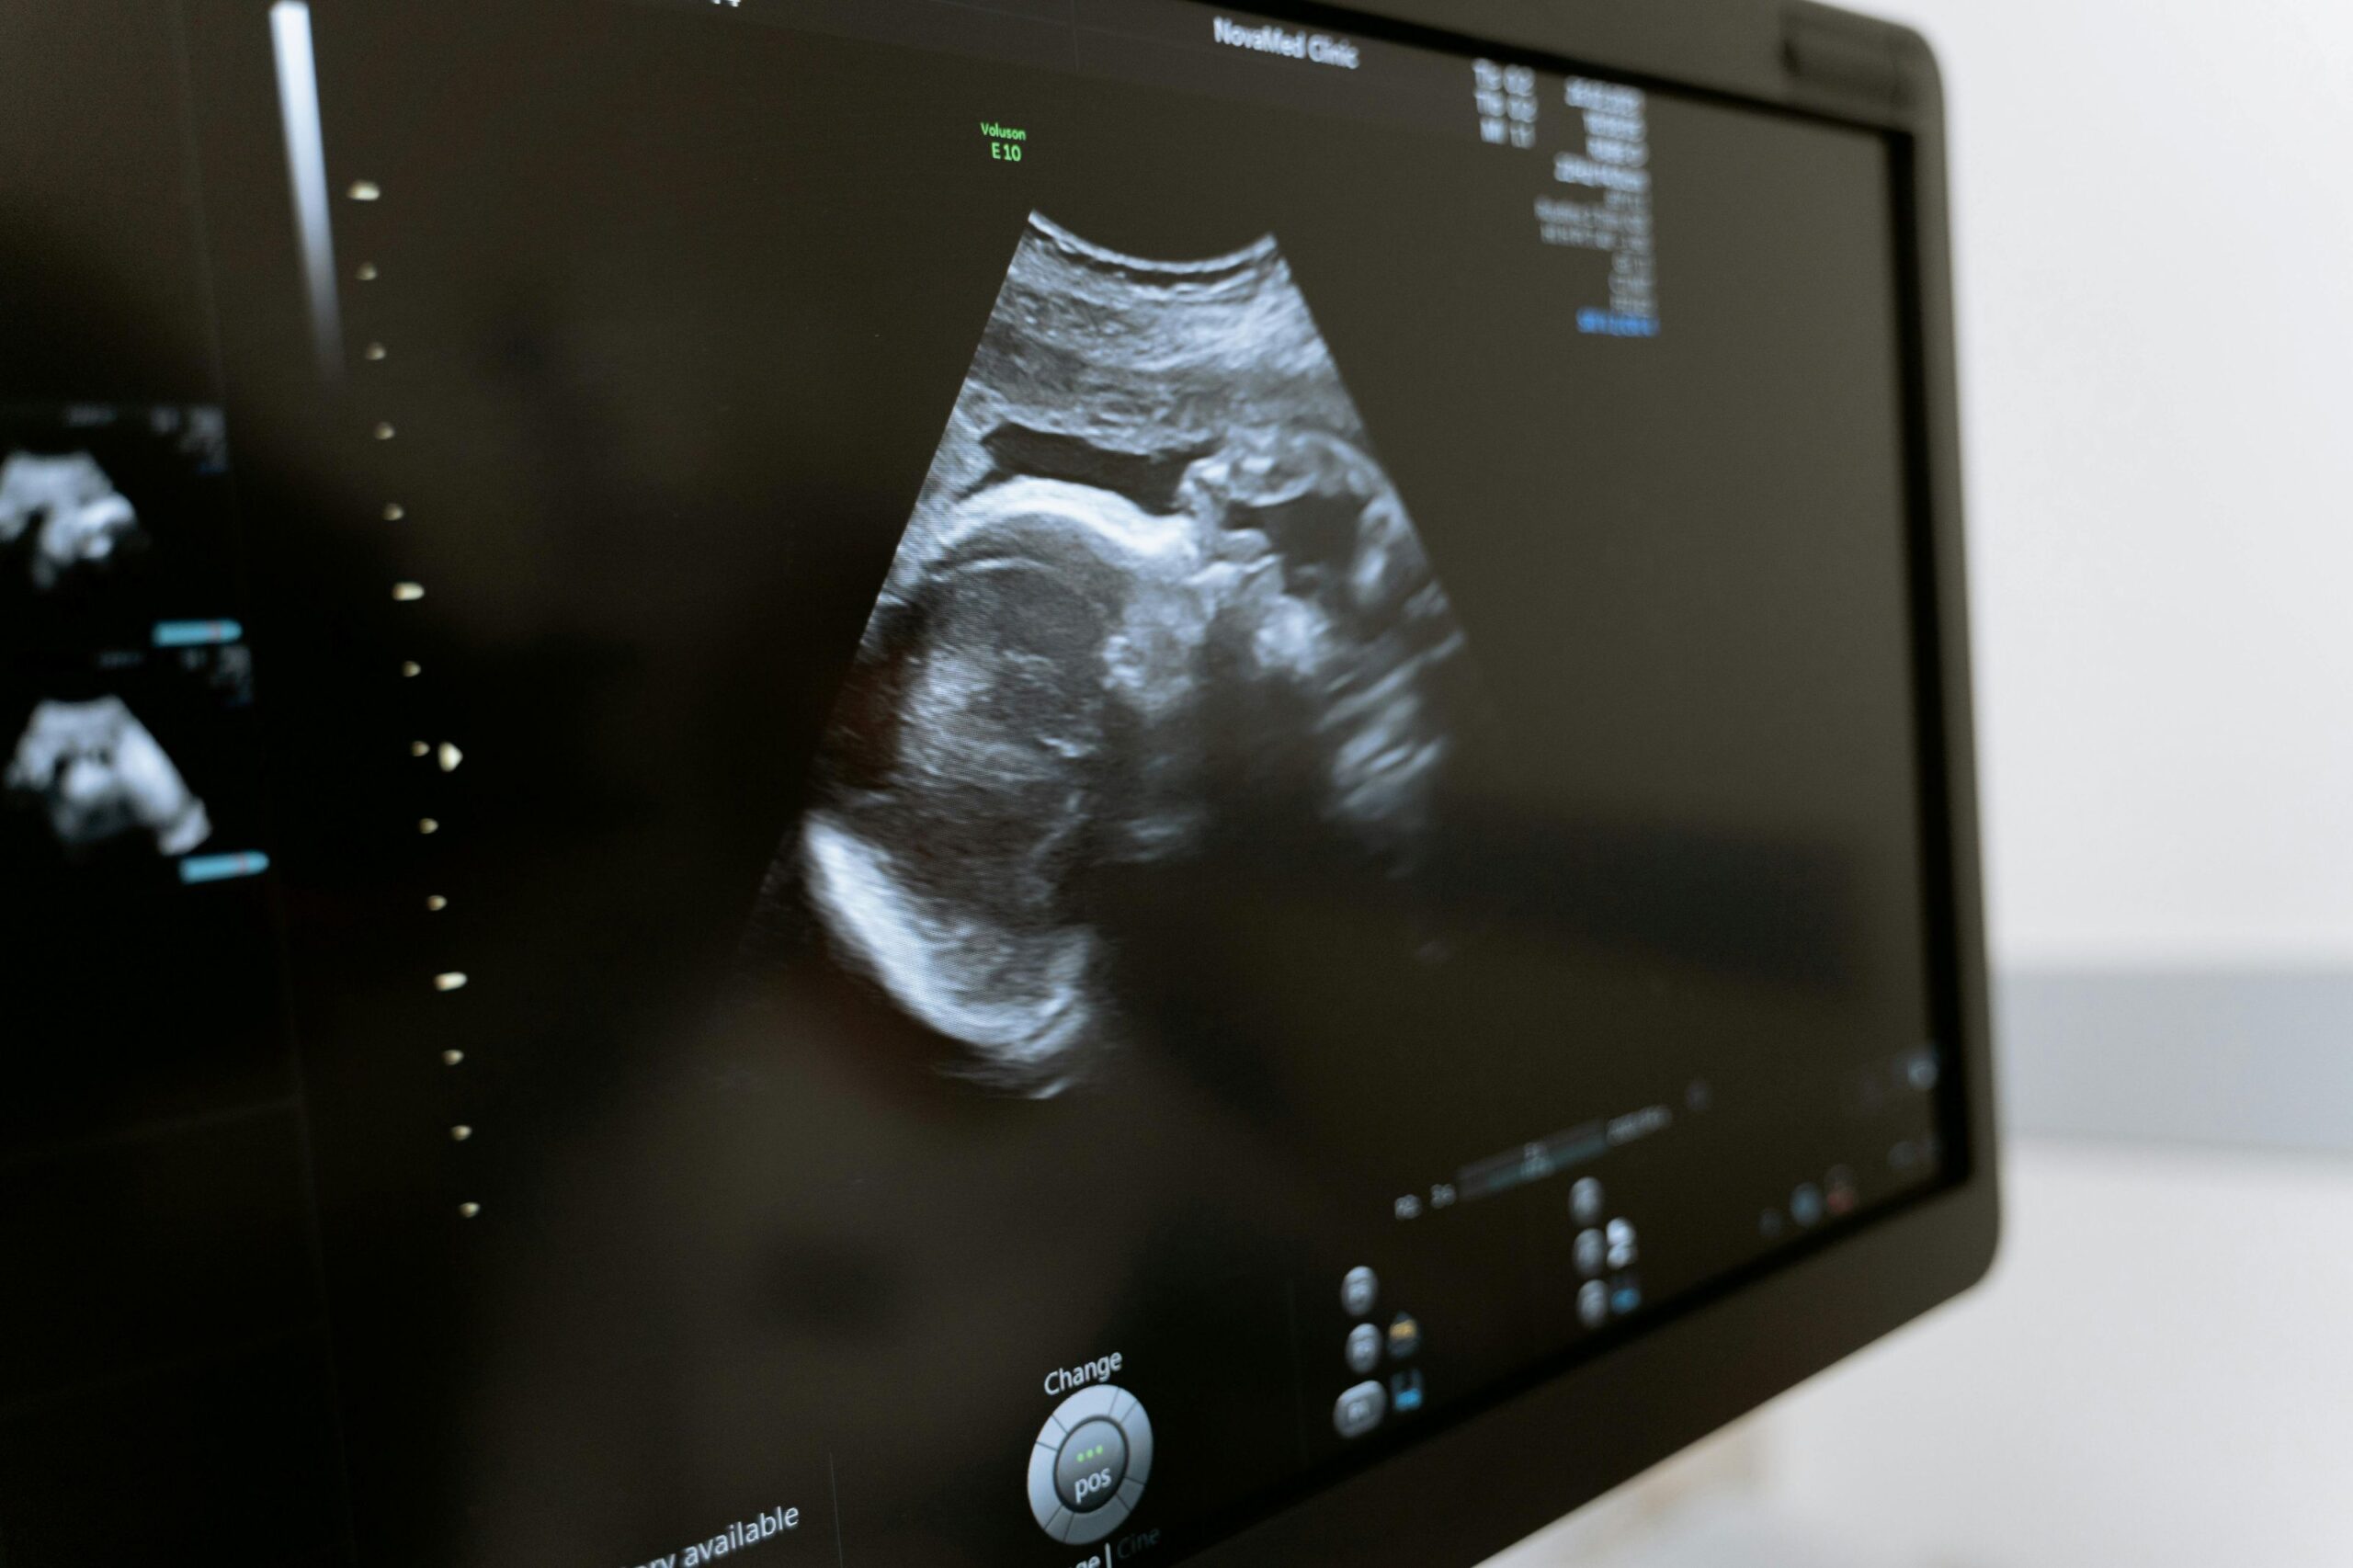

Die pränatale Ultraschalldiagnostik hat sich in den letzten Jahren rasant weiterentwickelt und spielt auch 2026 eine zentrale Rolle in der Schwangerschaftsbetreuung. Moderne Ultraschallverfahren bieten heute nicht nur Einblicke in die Entwicklung des Fötus, sondern unterstützen Ärztinnen und Ärzte dabei, potenzielle Risiken frühzeitig zu erkennen. Für werdende Eltern wird die Untersuchung damit zu einem wertvollen Instrument,…